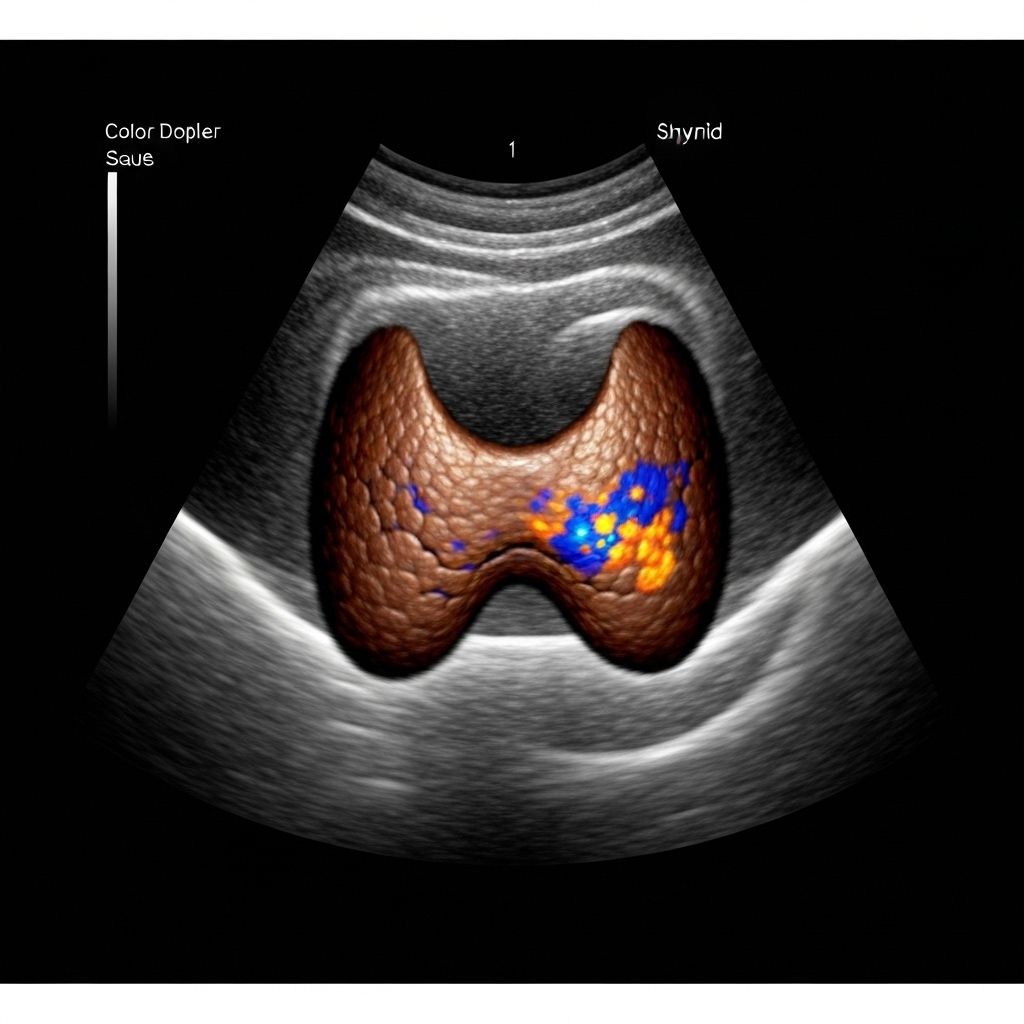

Dedicated small-parts ultrasound for thyroid, breast, scrotal, musculoskeletal, and superficial lesions using high-frequency probes.